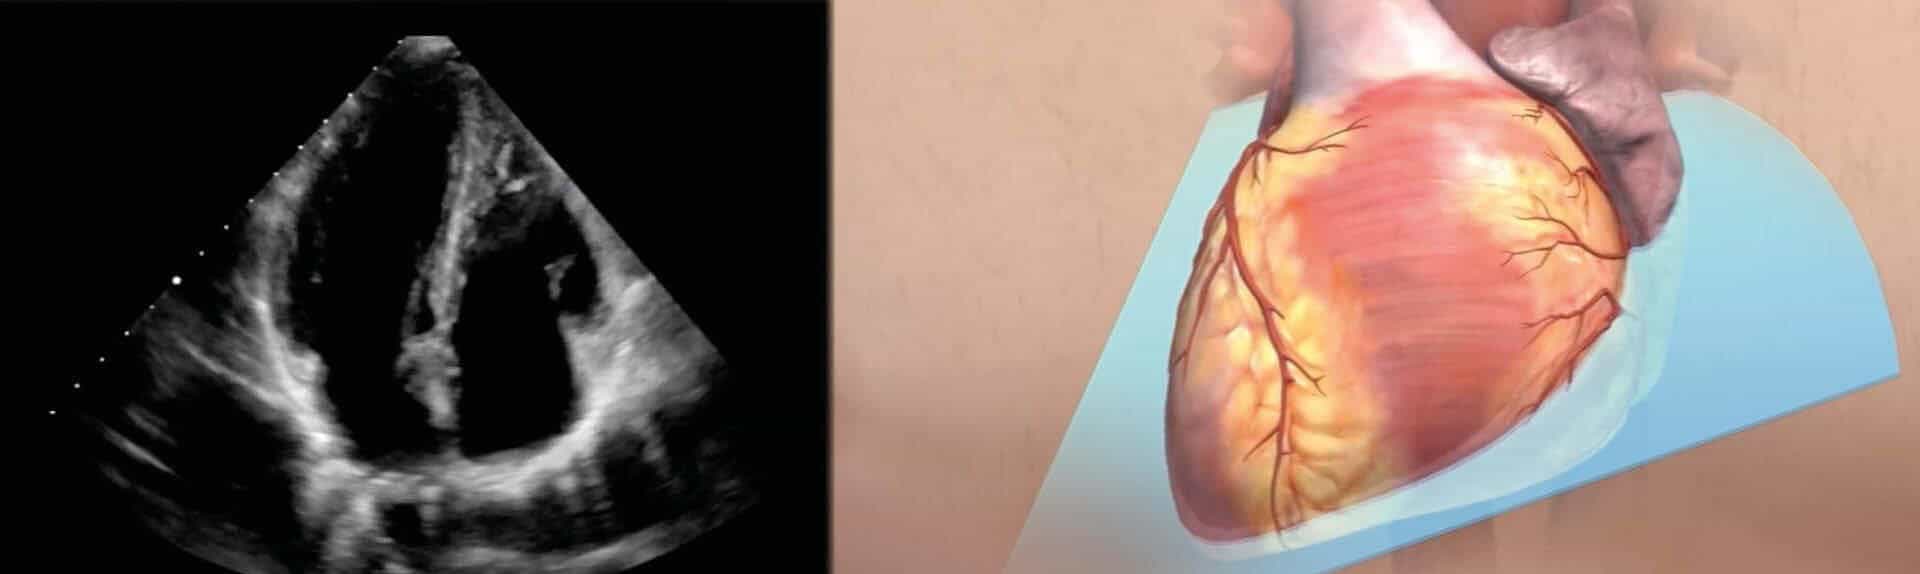

2D Ultraschall: Schnittebenen im Herzen

Bei der transthorakalen Echokardiographie legt der Arzt verschiedene Schnittebenen ins Herz. Dadurch kann der Untersucher alle Abschnitte des Herzmuskels, die Herzklappen und auch großen Herzgefäße durch die Brustwand untersuchen. Die nachfolgende Abbildung zeigt, welche Einblicke die unterschiedlichen Schall-Ebenen ermöglichen.

Die transthorakale Echokardiographie wird üblicherweise bei entkleidetem Oberkörper in Linksseitenlage oder Rückenlage durchgeführt. Dadurch kann das vor dem Herzen liegende Lungengewebe zur Seite gleiten und dadurch die „Sicht“ auf die darunterliegenden Herzstrukturen freigegeben. Luft stört die Untersuchung, das ist auch der Grund, warum eine Herzultraschall – Untersuchung nicht sofort nach Einnahme dieser Position beginnen sollte. Für bestimmte Fragestellungen muss der Patient gegebenenfalls andere Positionen einnehmen (z.B. Rückenlage, Rechtsseiten-Lage: s. Video)